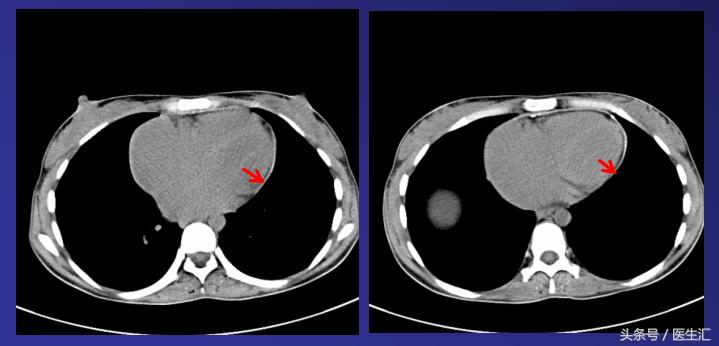

2011-11-18胸部CT:双房增大,心包均匀增厚,可见明显钙化灶,考虑缩窄性心包炎。

治疗:2011-11-29行心包剥脱术,术中见心包显著增厚,壁、脏层心包粘连紧密,无积液。最致密处位于心脏膈面及右房室沟,心包最厚约10mm,质地坚硬,散在少量钙化。

心包病理:纤维结缔组织增生并玻璃样变,符合缩窄性心包炎改变